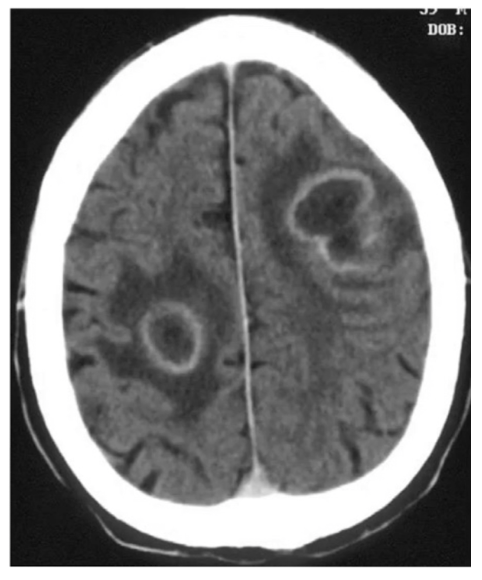

CT protocol + Pathology?

• Brain C-

• Abscess: fluid filled pockets of infection within the brain parenchyma

• Ring like structure where the hypodense inner ring is pus and the hyperattenuating outer ring is other fluid.

• Adjacent phasogenic oedema.